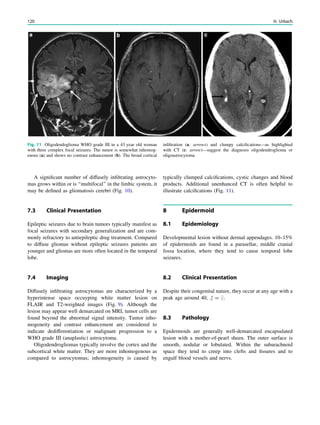

Fig. 2 Epileptogenic lesion and symptomatogenic zone. A 40-year-

old woman suffered from complex focal seizures with a fearful face

and body rocking. The symptoms thus pointed to the mesial frontal

lobe as the origin. MRI shows right-sided hippocampal sclerosis

(a, arrow). Simultaneous video and EEG recordings from interhemi-

spheric (c) and convexity strip and intrahippocampal depth (b) elec-

trodes show seizures starting in the right hippocampus (d, arrow).

Clinical symptoms start around 1 s afterwards (d, asterisk)